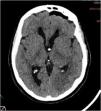

An extremely rare complication of endoscopic colloid cyst removal is presented. Terson’s syndrome related to endoscopic resection of a colloid cyst has been reported only twice before in the literature and it could be explained by intracranial hypertension related to rinsing during the procedure. The case is described and the complications in the neuroendoscopic removal of colloid cyst are reviewed from the literature.